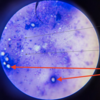

Leishmania sp.: Promastigotes

- Leishmania sp.*: Promastigotes

- Extracellular forms*